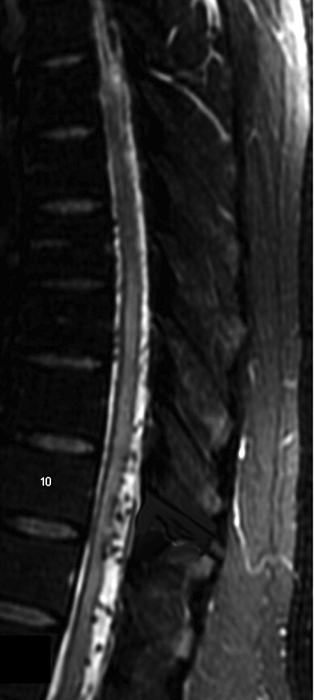

Q7: A 75-year-old woman with history of prior cervical spine decompression presented with progressive neck pain, asymmetric hand tingling, and neuropathic pain, followed by urinary incontinence and gait difficulty. Sagittal T2 weighted imaging likely shows?.